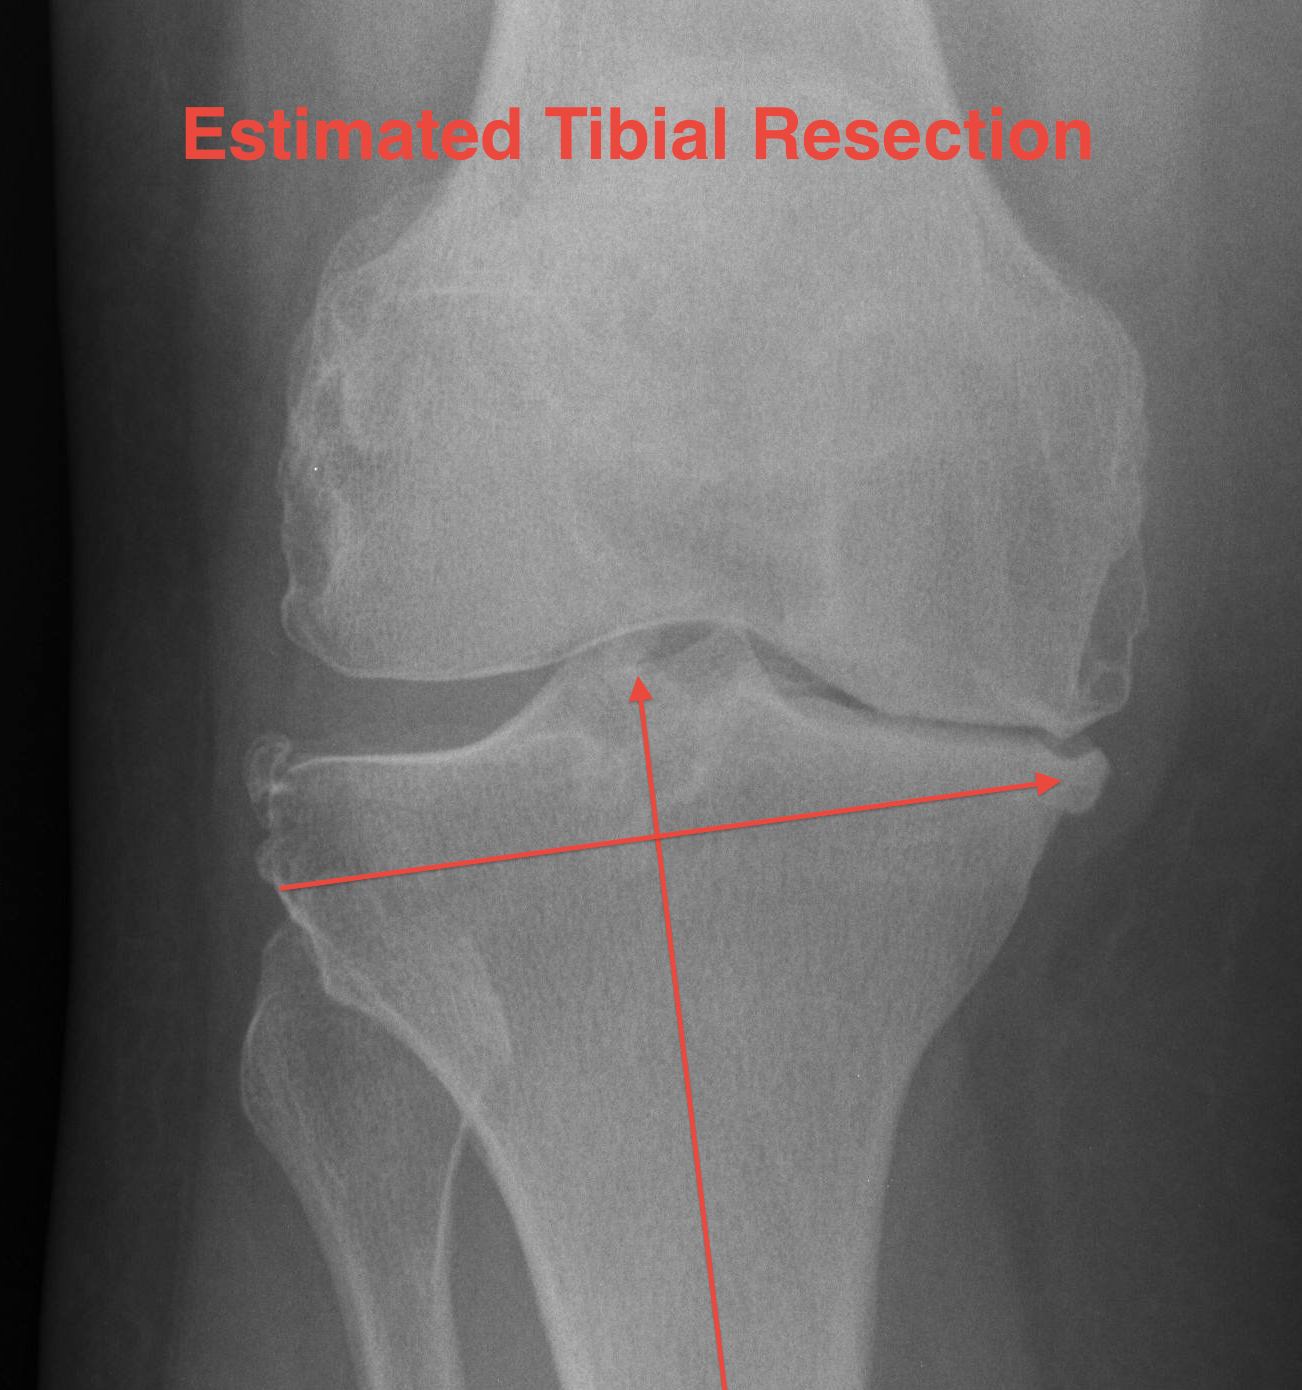

Tibial Bone Cut

Alignment

Intramedullary guide

- less accurate with any tibial deformity

Extra-medullary guide

- most accurate

Extramedullary Alignment

Maximally flex knee

- retractors each side

- forked tongue, blunt homans retractor behind tibia to sublux forward

Centre jig at knee

- pin centre of interspinous eminence

- junction middle / medial two thirds tibial tubercle

- impact first pin on jig

Set rotation at knee

- rotate to tibial crest

- impact second proximal pin on jig

Tibial component rotation

A. Internal rotation of component

- will give valgus due to posterior slope

- results in tibial ER & increased Q angle

B. Cut tibia when ER

- posterior slope creates varus

C. Cut tibia when IR

- posterior slope creates valgus

Centre jig over talus

- line up with second MT

- halfway between medial malleolus and anterior fibula

- between EHL / EDL

- always tend to go towards medial malleolus to avoid varus which is most common mistake

- should align over tibial crest

Posterior slope

Normal posterior slope is 10o

- decreased by menisci to 3o

If tibia is cut at 90o, increased risk of tibial subsidence

- if flat poly design, cut at 10o

- if oblique poly design, can cut at less

Bone anteriorly is poor

- therefore usually wish to cut with a posterior slope to preserve anterior bone

- degree of posterior slope also built into poly

Set resection depth

Options

- resect 2 mm from worn side (medial)

- resect 10 mm from normal side (lateral)

- use stylus

Best to cut from lateral side

- have set joint line distally on femur from lateral side

- best to continue to do so from lateral side

- in a varus knee the medial joint line is worn

- lateral joint line is usually preserved

- enables preservation of anatomic joint line